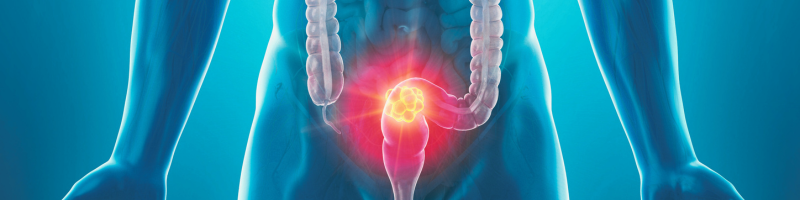

O mês de março destaca a campanha Março Azul Marinho, uma iniciativa essencial para alertar a população sobre a prevenção e o combate ao câncer colorretal. Essa doença, que afeta o intestino grosso e o reto, está entre os tipos de câncer mais comuns no Brasil. De acordo com o Instituto Nacional de Câncer (INCA), cerca de 46 mil novos casos são diagnosticados anualmente, tornando a conscientização ainda mais necessária.

O câncer colorretal se origina do crescimento anormal de células no cólon, reto ou ânus. Na maioria dos casos, ele surge a partir de pólipos intestinais, que podem evoluir para tumores malignos se não forem removidos precocemente. Embora muitas pessoas não apresentem sintomas nas fases iniciais, a detecção precoce aumenta consideravelmente as chances de cura.